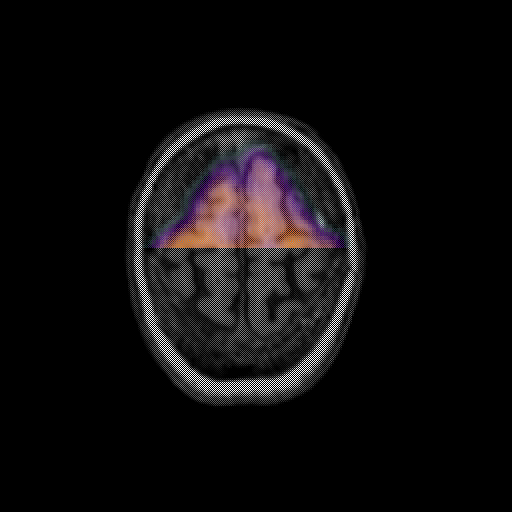

overlay: Slice 46

Slice 46

MRCBFCBF with

T1PDT2T1PDT2